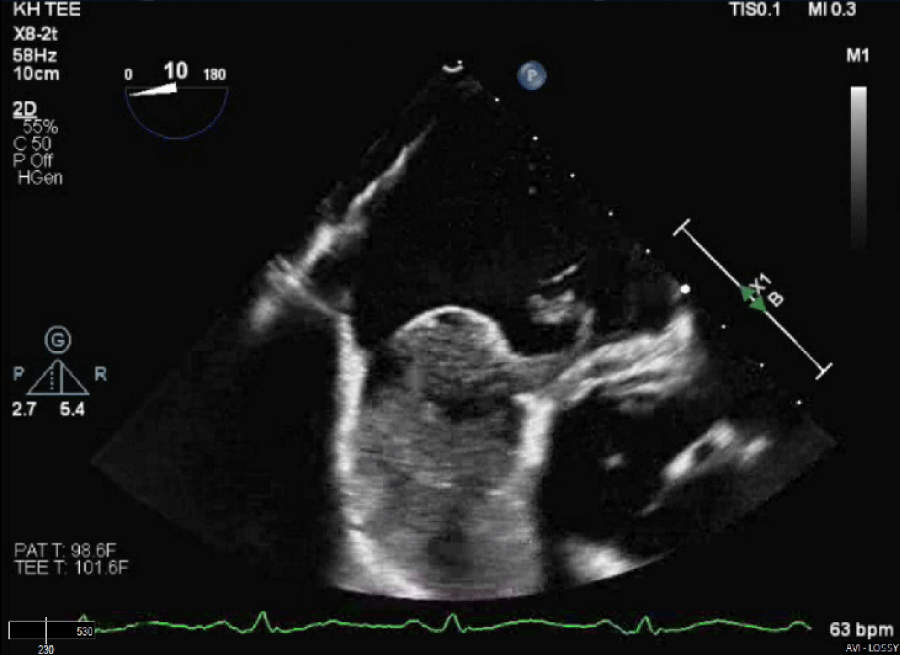

The patient’s clinical condition was consistent with Platypnea-Orthodeoxia syndrome based on the findings described above. A transthoracic echocardiogram indicated an ejection fraction (EF) of 51-55%, with mild left ventricular hypertrophy (LVH) and mild right ventricular dilatation. The bubble study was inconclusive. A transesophageal echocardiogram (TEE) revealed that the interatrial septum was aneurysmal, and a large PFO was visible on color Doppler imaging and following the injection of agitated saline contrast, as shown in figures 1 and 2. The patient underwent transcatheter closure of a patent foramen ovale using a 30 mm Gore Cardioform device, as depicted in figure 3 and 4. Immediately after the procedure, a repeat bubble study was conducted, which showed no bubbles crossing the patent foramen ovale (PFO). He was placed on dual antiplatelet therapy, with aspirin and clopidogrel for one month, followed by aspirin indefinitely. On the day of discharge, the patient was sitting upright in bed with oxygen saturation levels at 94% on room air and reported no shortness of breath. The patient was feeling much improved. The patient's care in the hospital involved a multidisciplinary approach that included teams from cardiology, pulmonology, and hospital medicine. Following hospital discharge, the patient had follow-up appointments in both the cardiology and pulmonary clinics and underwent a transthoracic echocardiogram (TTE) one month after the procedure. The left atrial cavity is moderately dilated. No patent foramen ovale was detected during the agitated saline injection. The patient did not report any breathing issues, and his oxygen saturation on the day of the follow-up was 94%.

Figure 2: TEE with PFO defect. View Figure 2